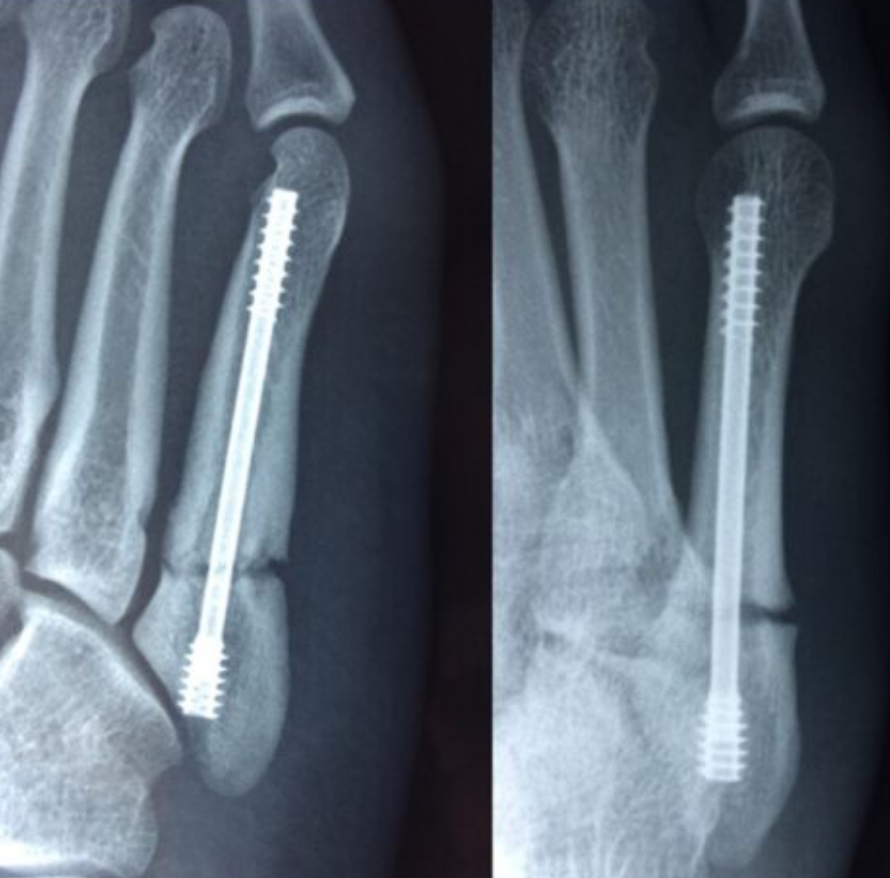

2020-12-09 スポーツ整形 ページ内リンク 第5中足骨骨折(ジョーンズ骨折)【スポーツ整形外科】 第5中足骨骨折(ジョーンズ骨折)【スポーツ整形外科】 サッカーやバスケット等の切り返しの多い競技にしばしば発生する。⇒スクリューによる固定で2〜3か月で復帰。 術前 術後 術後12週間 杉本 武 副院長/スポーツ整形外科センター長 整形外科スポーツ整形 詳しく見る 板野 佑生 整形外科スポーツ整形 詳しく見る 関連ページ スポーツ整形 一覧へ戻る